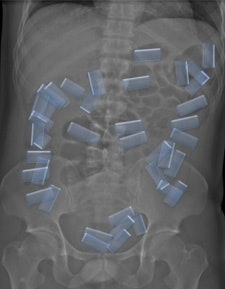

Abdominal CT scans were overwhelmingly superior to the other modalities, with 100% sensitivity, 94.1% specificity, 94.7% positive predictive value (PPV), and 100% negative predictive value (NPV). This was true for imaging of all three types of suspects: "body packers," who swallow a large amount of packets for gastrointestinal tract passage; "body pushers," who hide drugs in bodily orifices; and "body stuffers," who ingest small amounts of loosely wrapped drug pellets if they suspect that are about to be intercepted.

There were a total of 54 drug carriers, or 65% of the total taken in custody. All who had CT exams were positively identified, a total of 23. However, one innocent person was misidentified.

Capsules holding cocaine are of different densities. It is important to perform window-level adjustments to detect drug containers, according to the authors. It also helps for a radiologist to know what the typical size and appearance are of different cocaine containers. With this knowledge, they can be better distinguished from normal intestinal gas, calcifications, scybala, and other foreign bodies.

The authors noted that it was also important for a radiology report to contain a precise description of the number of drug containers that are identified, and to indicate where they are located in the intestinal tract. This makes the job of the feces evaluators easier.